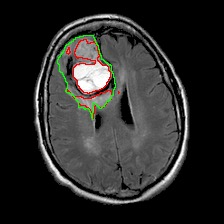

Neural processes have recently emerged as a class of powerful neural latent variable models that combine the strengths of neural networks and stochastic processes. As they can encode contextual data in the network's function space, they offer a new way to model task relatedness in multi-task learning. To study its potential, we develop multi-task neural processes, a new variant of neural processes for multi-task learning. In particular, we propose to explore transferable knowledge from related tasks in the function space to provide inductive bias for improving each individual task. To do so, we derive the function priors in a hierarchical Bayesian inference framework, which enables each task to incorporate the shared knowledge provided by related tasks into its context of the prediction function. Our multi-task neural processes methodologically expand the scope of vanilla neural processes and provide a new way of exploring task relatedness in function spaces for multi-task learning. The proposed multi-task neural processes are capable of learning multiple tasks with limited labeled data and in the presence of domain shift. We perform extensive experimental evaluations on several benchmarks for the multi-task regression and classification tasks. The results demonstrate the effectiveness of multi-task neural processes in transferring useful knowledge among tasks for multi-task learning and superior performance in multi-task classification and brain image segmentation.